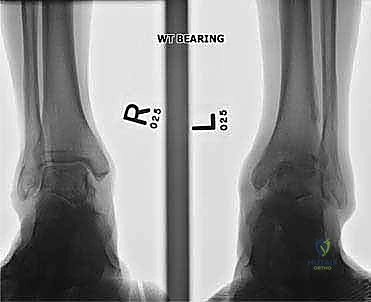

التصوير الطبي المتقدم (Medical Imaging)

لتأكيد التشخيص ووضع الخطة الجراحية، يتم الاعتماد على أحدث تقنيات التصوير:

- الأشعة السينية أثناء الوقوف (Weight-bearing X-rays): هي الفحص الذهبي والأهم. يجب أن تؤخذ الأشعة والمريض واقف لتحمل الوزن. تظهر الأشعة تضيق المسافة المفصلية (دليل على فقدان الغضروف)، وجود نتوءات عظمية، تصلب العظم، وأي انحراف في محور المفصل.